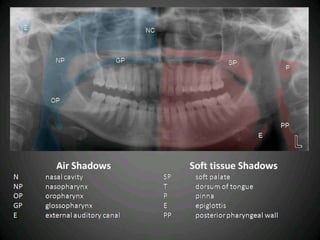

N

SP

P

PP

NP

E

OP

GP

CS